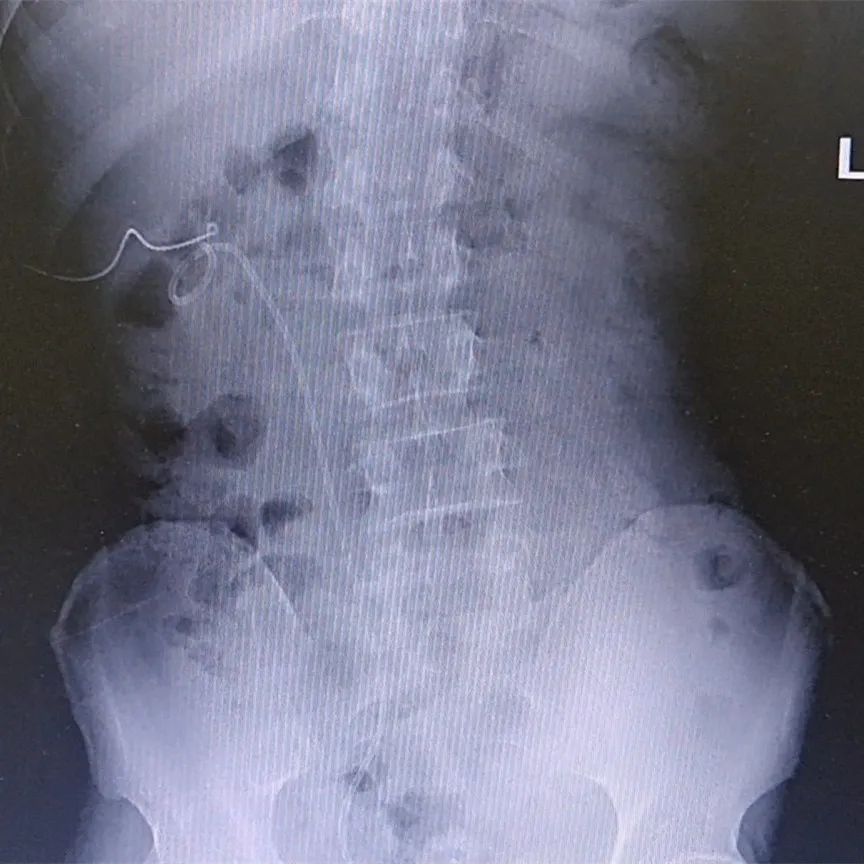

术后复查X片

结石已清除干净